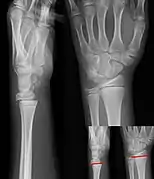

Salter–Harris I fracture of distal radius.